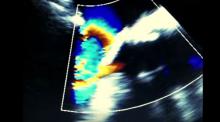

The Seldinger technique was utilized to cannulate the ascending aorta and the right femoral vein to establish cardiopulmonary bypass. The aorta was cross-clamped and the heart was arrested with a 2-liter single dose of HTK-Custodiol cardioplegia. The aorta was transected above the sinotubular junction and the remaining cardioplegia was given directly into the coronary artery ostia. A traction suture on the aorta was placed to aid the exposure of the left atrial dome. An incision was made in the dome of the left atrium to expose the mitral valve. The valve was exposed with an Estech retractor. The anterior leaflet of the mitral valve was removed. A series of interrupted 2-0 Ethibond pledgeted sutures were placed into the annulus of the mitral valve. The prosthesis was lowered into place and the sutures were tied with a Cor-Knot. The dome was closed with 4-0 Prolene sutures in a continuous fashion in two layers. Attention was then switched to the aortic valve.